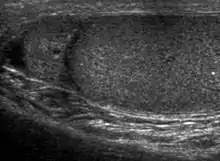

Seminoma is the most common tumor type in cryptorchid testes. The risk of developing a seminoma is increased in patients with cryptorchidism, even after orchiopexy. There is an increased incidence of malignancy developing in the contralateral testis too, hence sonography is sometimes used to screen for an occult tumor in the remaining testis. On US images, seminomas are generally uniformly hypoechoic, larger tumors may be more heterogeneous [Fig. 3]. Seminomas are usually confined by the tunica albuginea and rarely extend to peritesticular structures. Lymphatic spread to retroperitoneal lymph nodes and hematogenous metastases to lung, brain, or both are evident in about 25% of patients at the time of presentation.